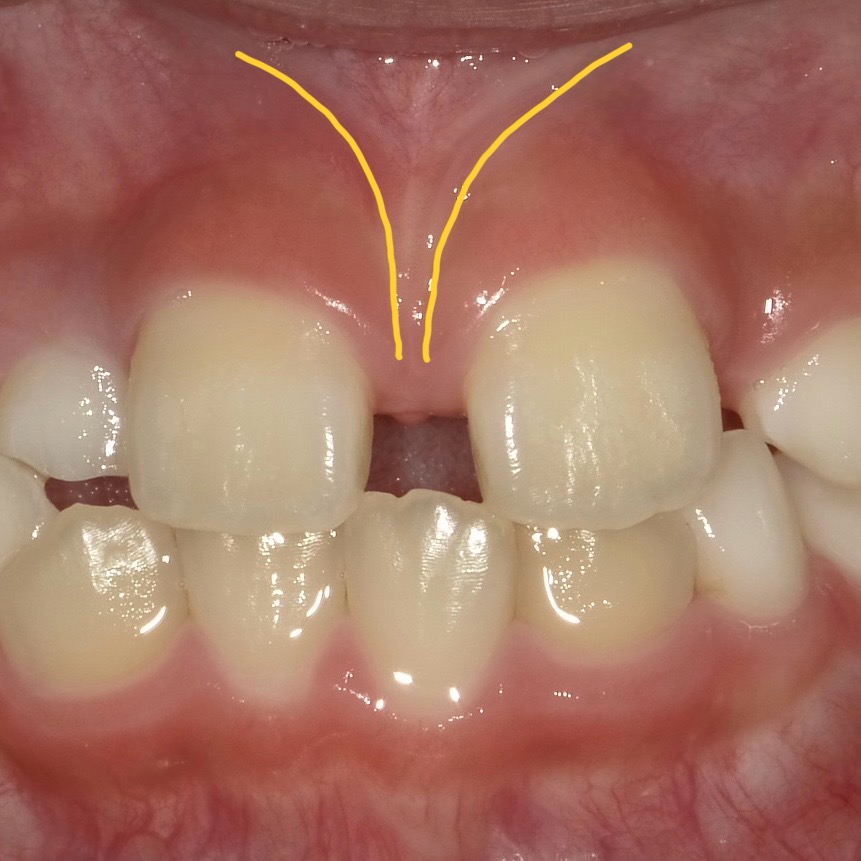

それぞれ以下のような状態です。

上唇小帯の高位付着